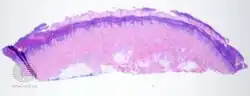

Talon noir-pathology -

Talon noir-pathology